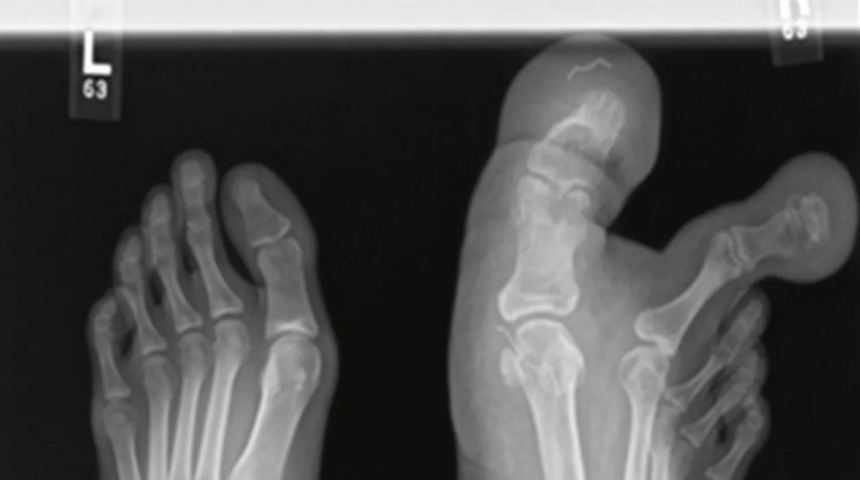

Malezya'nın başkenti Kuala Lumpur'da yaşayan ismi açıklanmayan 12 yaşındaki kız, sağ ayağının birinci ve ikinci ayak parmaklarını büyüten, devlik olarak da bilinen Macrodystrophia Lipomatosa (MDL) hastası olarak dünyaya geldi. Kalıtsal olmayan durum, fibroyağlı dokunun giderek büyümesine neden olarak anormal boyutlara ulaşmalarına neden olmasıyla biliniyor. Kendisine doğumda MDL teşhisi konulmasına rağmen ailesi tarafından kontrollerine getirilmeyen kız çocuğunun durumu gittikçe zorlaştı.

Kızın ailesi ayağındaki şekil bozukluğunun zamanla kötüleşmesi üzerine kızı hastaneye götürmeye karar verdi. Yürüme zorluğu yaşayan kızın durumunu inceleyen sağlık ekipleri, "Düz radyografiler ve MRI bulguları, birinci ve ikinci ayak parmakları çevresinde, birinci metatarsın medial ve lateral yönlerinde, ayağın medial plantar kemerine kadar uzanan yağ dokusu birikimini ortaya çıkardı.MDL çok nadir görülen bir konjenital lokalize devlik hastalığıdır ve cerrahi konsültasyon sıklıkla kozmetik nedenlerden dolayı yapılmaktadır" ifadelerini kullandı.